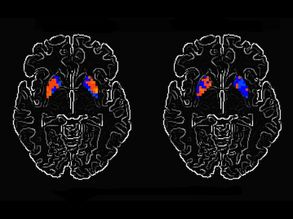

Genes to Brains

World Alzheimer's Day

21

Alleviating Alzheimer's